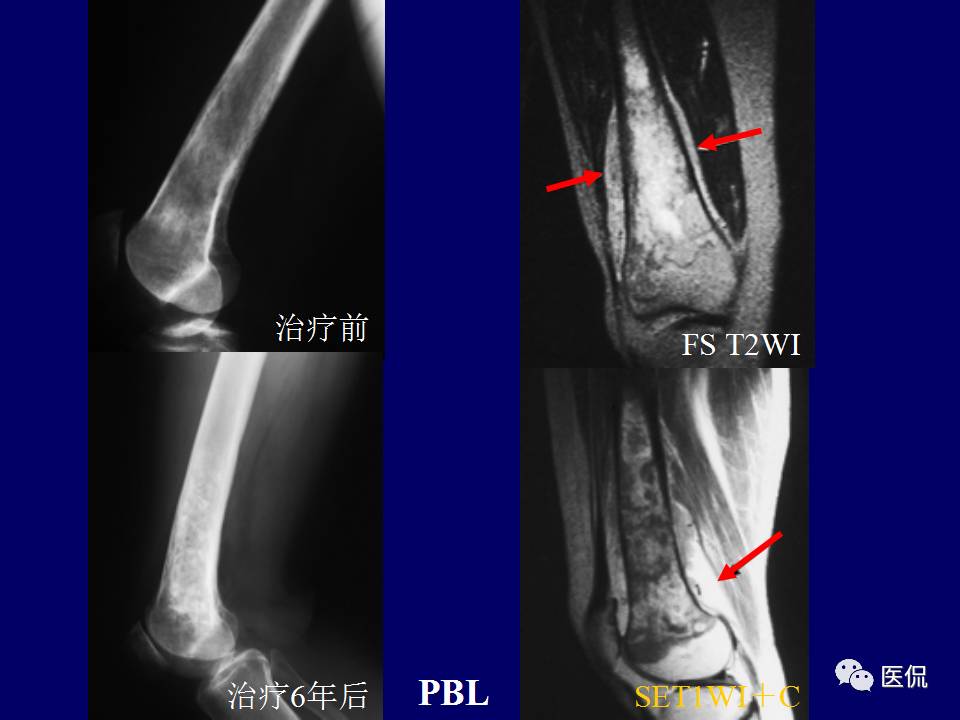

原发性骨淋巴瘤,是一种少见肿瘤。平片上干骺端单发、浸润性骨质破坏、层状骨膜反应+MR上骨髓侵犯、软组织肿块+年龄>30岁均可高度提示,影像学区分原发和继发PBL比较困难。更多知识,请往下看~